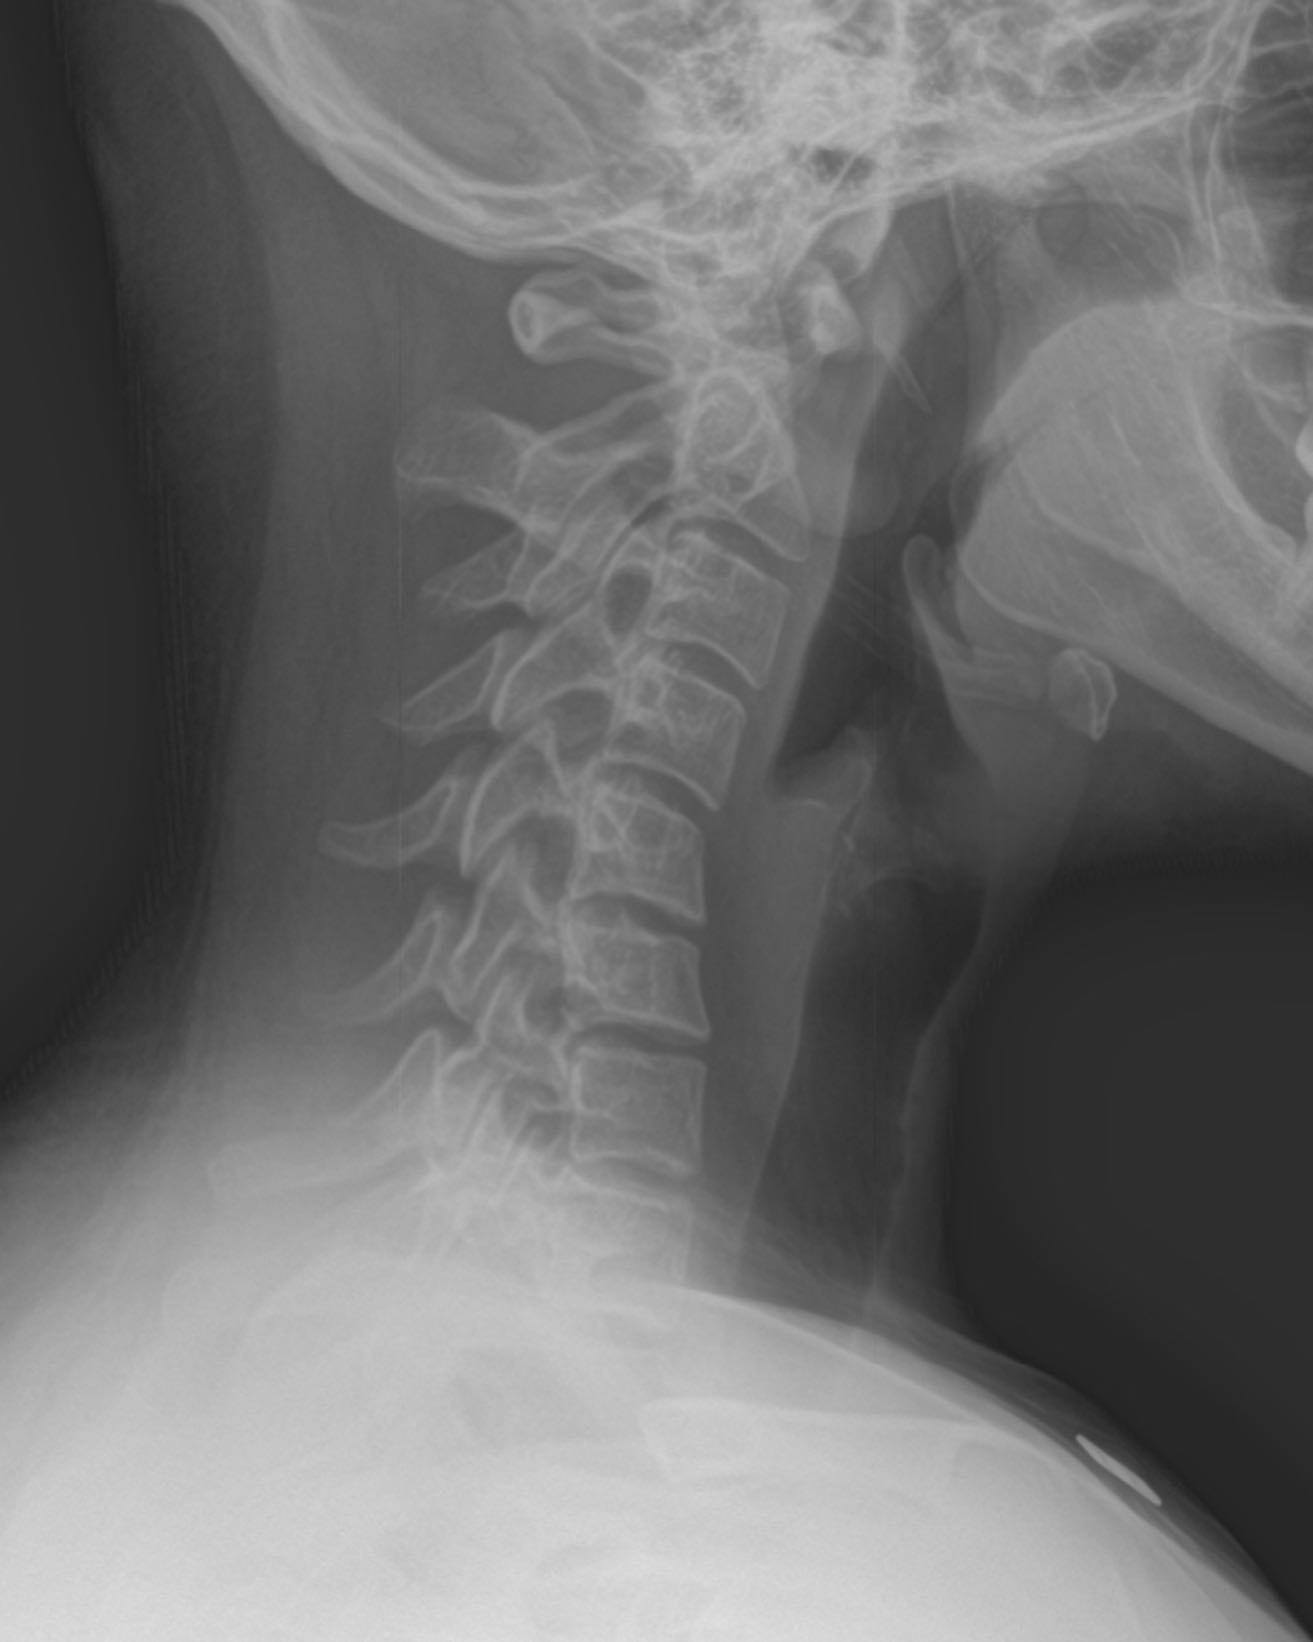

Often, chiropractic doctors will recommend a physical exam to diagnose your neck pain. A physical exam will help the doctor pinpoint the exact location of the pain and check the intensity and radiation. Our chiropractic doctors will also ask you about any recent neck injuries or activities that may have caused the problem. In some cases, a doctor will order imaging tests, such as an x-ray, to confirm the diagnosis.